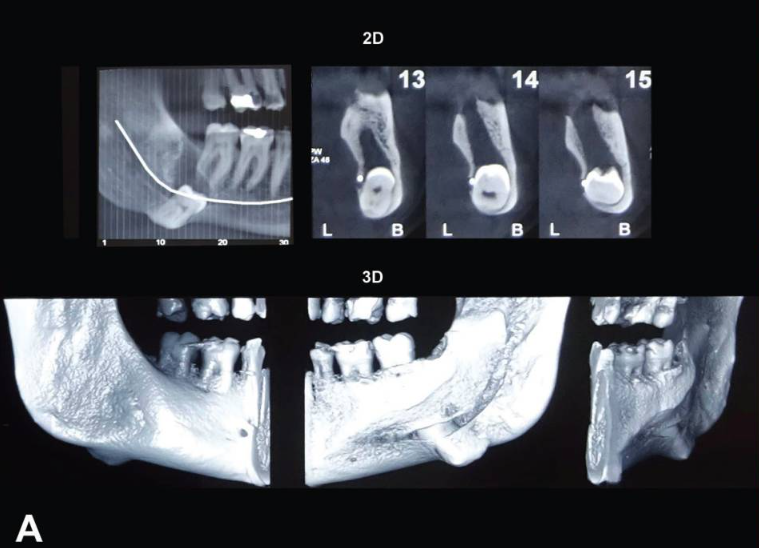

患者,女性,56岁,因右面部疼痛和开口困难被转诊至我们诊所。她提到,右下颌下缘区域的突出物已存在超过10年。患者的病史中没有并发症。初步的口外临床检查显示右下颌下缘有大面积的疼痛性炎症肿胀。全景X线片显示该区域存在一颗异位第三磨牙的深度阻生,伴有放射透亮的病变。锥形束计算机断层扫描(CBCT)进一步显示,阻生主要影响了下颌下缘的舌侧板(图1A)

A) 选取的患者锥形束计算机断层扫描(CBCT)2D和3D视图显示,阻生主要影响右下颌体下缘的舌侧板。